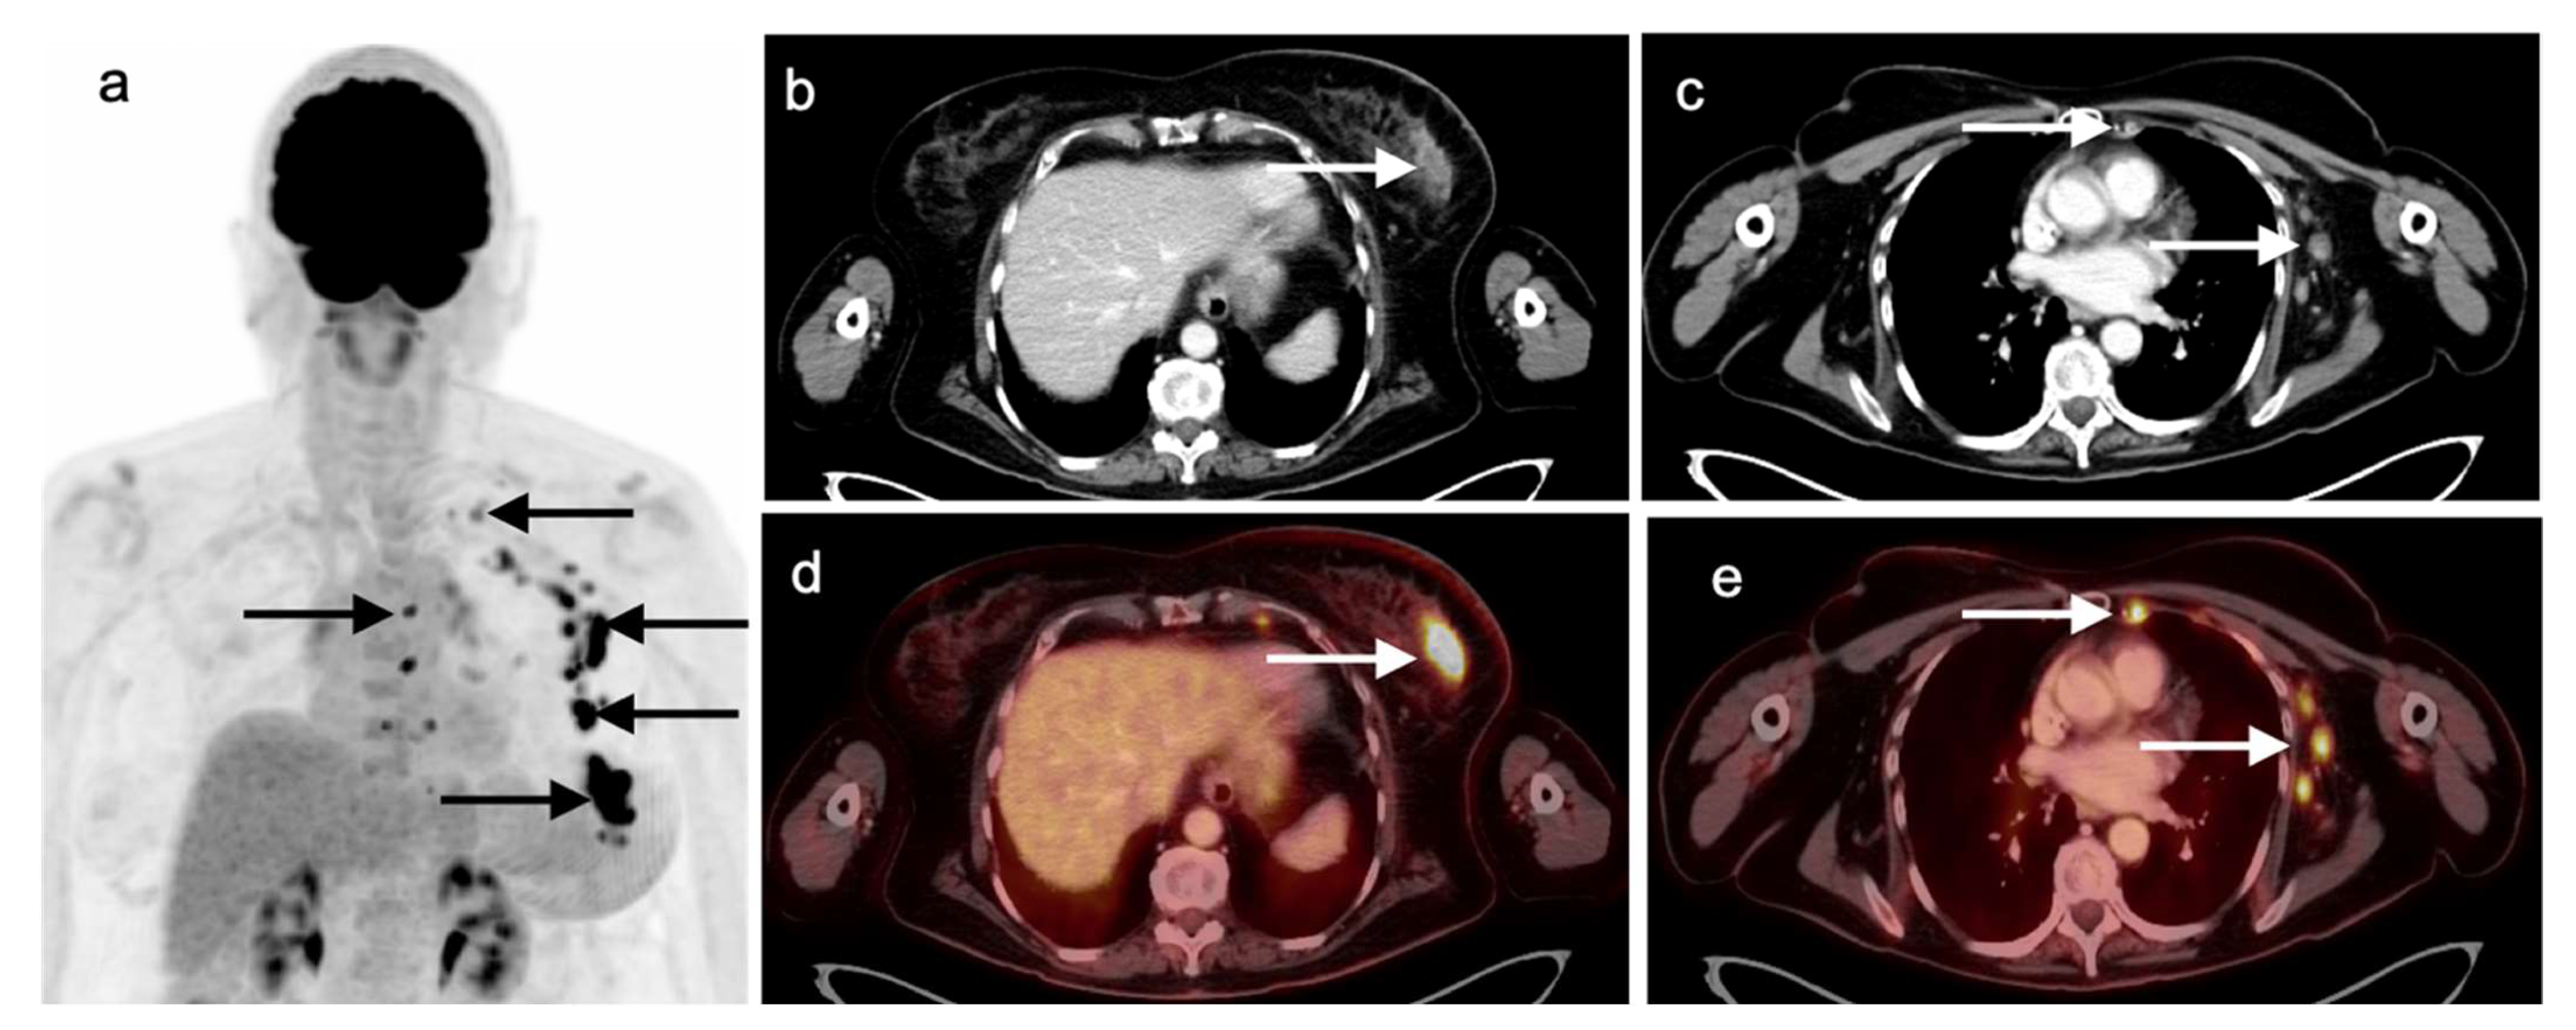

N staging identifies nodal involvement in lung cancer is of paramount importance, especially in patients with mediastinal disease without distant extra-thoracic disease. In these patients, the N stage will have therapeutic and prognostic implications [29]. In describing areas of nodal involvement, it is important to identify the specific nodal location involved, as outlined by the IASCL, as this will affect the N classification [26]. Patients staged as N0 or N1, without lymph node involvement, are generally treated with local intervention, and patients with N2 disease with ipsilateral mediastinal lymph node metastases might benefit from a combined approach with local and systemic therapies. N3 diseases with contralateral mediastinal lymph node metastases are considered incurable and will eventually require palliative care [2]. FDG PET-CT has advantages over CT alone, even when the lymph nodes are smaller than 10 mm in diameter [2,30]. FDG PET-CT is of crucial importance in evaluating nodal sites that are inaccessible to mediastinoscopy, such as the aortopulmonary window, anterior mediastinum, and posterior subcarinal nodes. Even though FDG PET-CT is an excellent noninvasive imaging modality in the detection of nodal metastatic involvement, mediastinoscopy remains the gold-standard and needs to be performed wherever there is ambiguity or uncertainty with regard to the status of any one lymph node in patients with NSCLC (Figure 9).

Nearly half of all patients with NSCLC have distant metastatic disease at initial diagnosis and identification of distant metastases is of major importance in the management and prognosis. Additionally, among patients who have been treated with radical and supposedly curative therapy, approximately 20% are likely to develop recurrent disease due to undetected foci of metastasis at initial M staging. Distant metastases are most commonly seen involving the brain, skeleton, liver, and adrenal glands in descending order of frequency (Figure 10) [31]. Traditional evaluation for distant metastatic disease includes CT scans of chest, abdomen, and pelvis, brain imaging with CT or MRI and bone scintigraphy [2]. However, FDG PET-CT has been shown to be great utility in M staging of the patients with NSCLC, specifically if the patients present with clinical manifestations of metastatic disease. Additionally, FDG PET-CT has been shown to provide more pertinent information during the preoperative assessment than is CT alone, except in the assessment of brain metastases, in a situation where the two modalities yield similar results [32]. For staging mediastinal lymph nodes, diffusion-weighted imaging MRI (DWI) and FDG PET-CT showed similar performance in staging of mediastinal lymph nodes, supporting the idea that DWI may offer an alternative to FDG PET-CT in some cases [33].